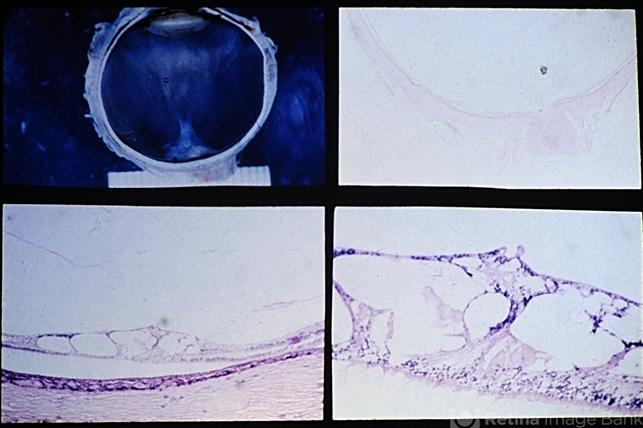

- cystoid, vitreous

- Cystoid degeneration of the retina in the macular area resulting from localized vitreous traction.